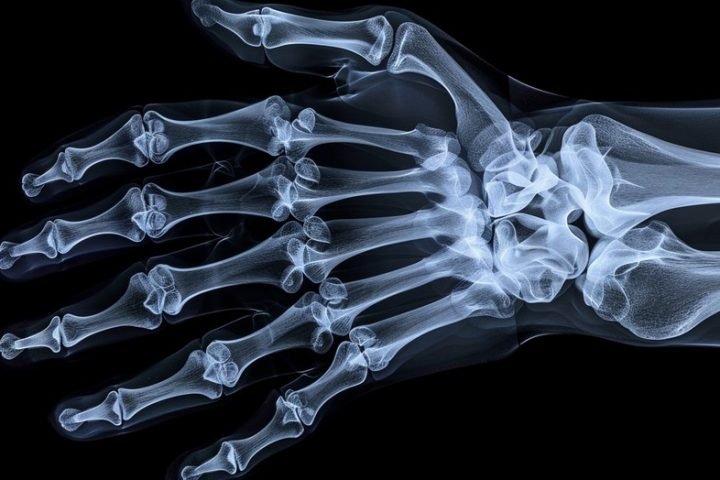

Bone Mineral Density diagnostic medical camp at Itoozhi Ayurveda, Mayyil

Itoozhi Ayurveda, Mayyil, recently organized a Bone Mineral Density (BMD) diagnostic camp on 8 September 2024, with a special emphasis on serving the immediate community.